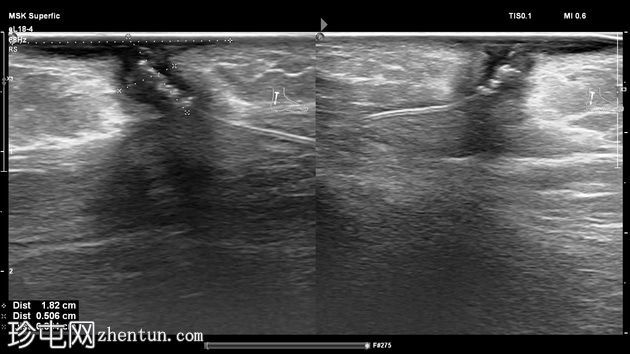

超声检查

1.jpg

斜位

左足跟皮下组织内可见一管状高回声物质,呈串珠状,与手术缝线相符,周围环绕着低回声积液。与缝线相连的是一根细细的、呈轨道状的高回声合成单丝,它穿过跟腱呈弧形走行,该缝线为不可吸收缝线。